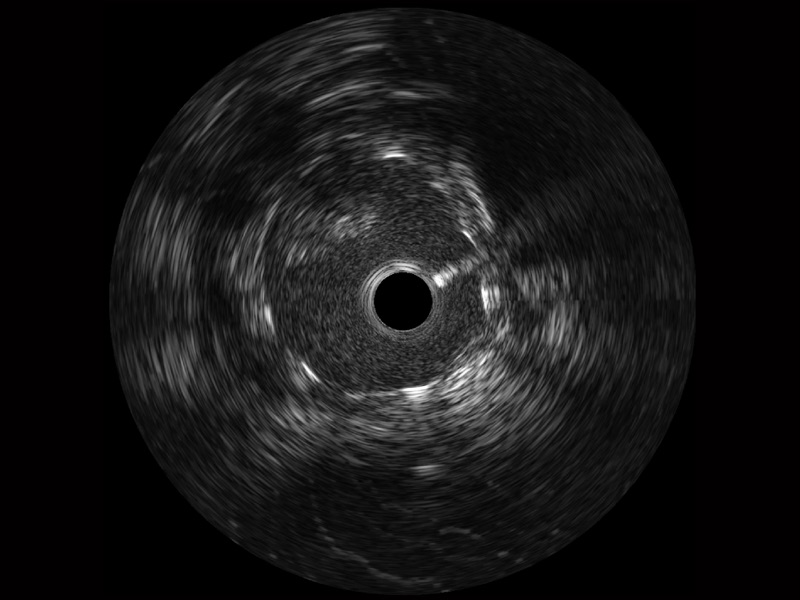

乐玩lewin国际宽频IVUS图像

传统IVUS图像

对比传统IVUS导管成像,乐玩lewin国际宽频IVUS图像的近场支架梁显影更细腻,远场中膜外血管仍清晰可辨,兼顾远中近,兼顾分辨力与穿透深度